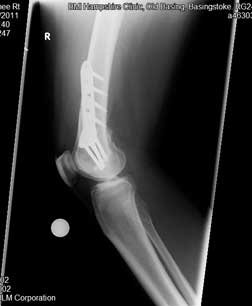

These are the two X-rays showing the femur with the plate in position from the front (left image) and the side (right image).

After the osteotomy, he was on crutches for six weeks protecting it because it was a femoral osteotomy (we protect femoral osteotomy with protected weight bearing on crutches for 6 weeks unlike tibial osteotomy where patients are allowed to fully weight bear without crutches from day 1 following surgery) . The ‘range-of-motion’ pictures were taken when he had been off his crutches for six weeks.